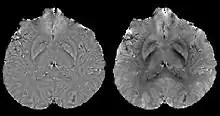

COSMOS assumes a model-free susceptibility distribution and keeps full fidelity to the measured data. This method has been validated extensively in in vitro, ex vivo and phantom experiments. Quantitative susceptibility maps obtained from in vivo human brain imaging also showed high degree of agreement with previous knowledge about brain anatomy. Three orientations are generally required for COSMOS, limiting the practicality for clinical applications. However, it may serve as a reference standard when available for calibrating other techniques.

MEDI has also been validated extensively in phantom, in vitro and ex vivo experiments. In in vivo human brain, MEDI calculated QSM showed similar results compared to COSMOS without statistically significant difference.[15] MEDI only requires a single angle acquisition, so it is a more practical solution to QSM.